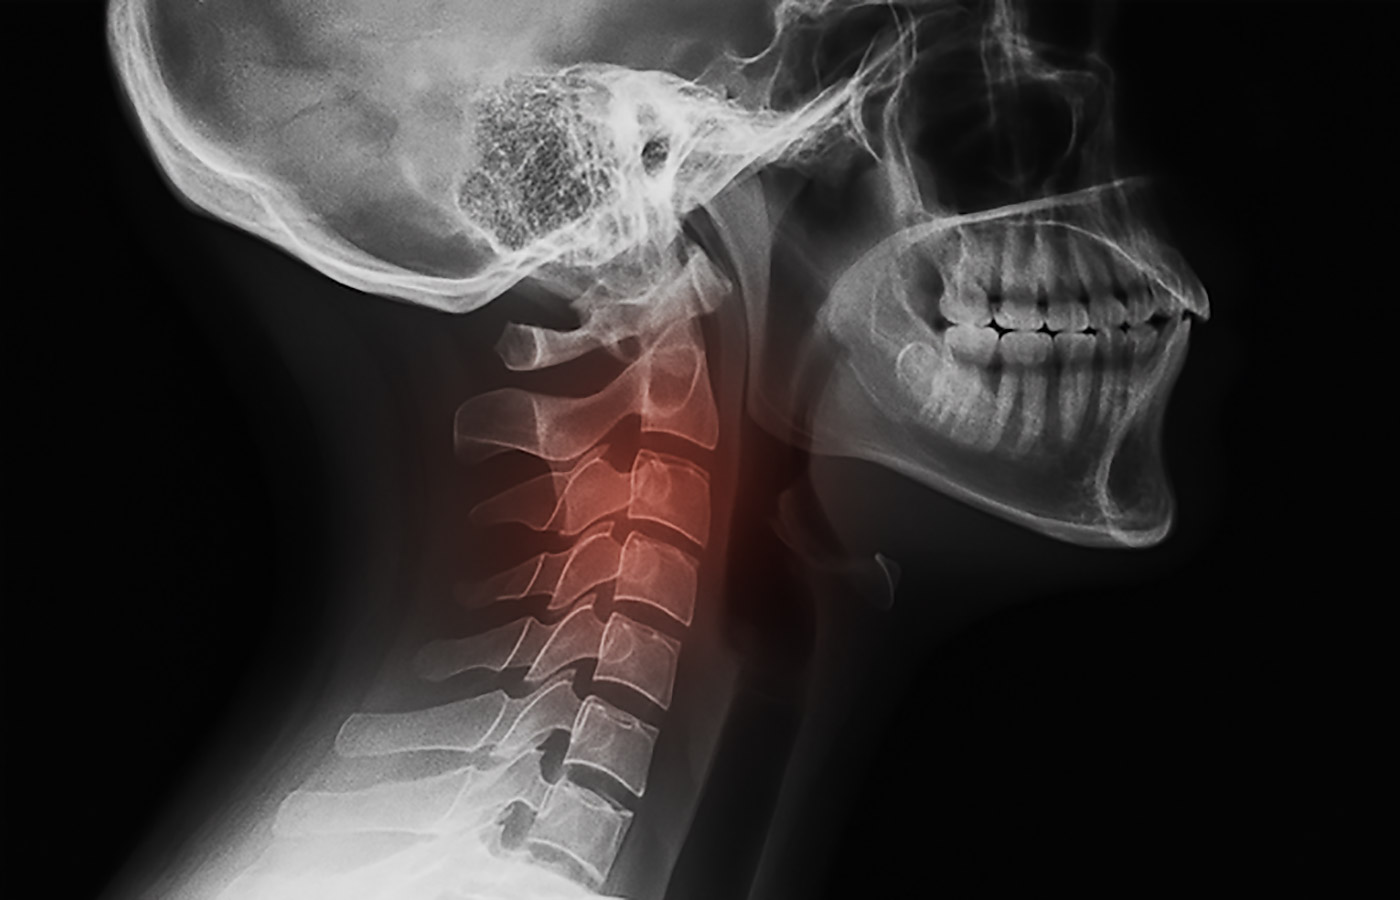

X-ray Findings (Taken on 1/23/2025):

- Grade 1 anterolisthesis of C2 on C3. An overall improvement of 50%. Indicating healingof the ligaments of that segment. (See images #2)

- Other findings not noted in this study